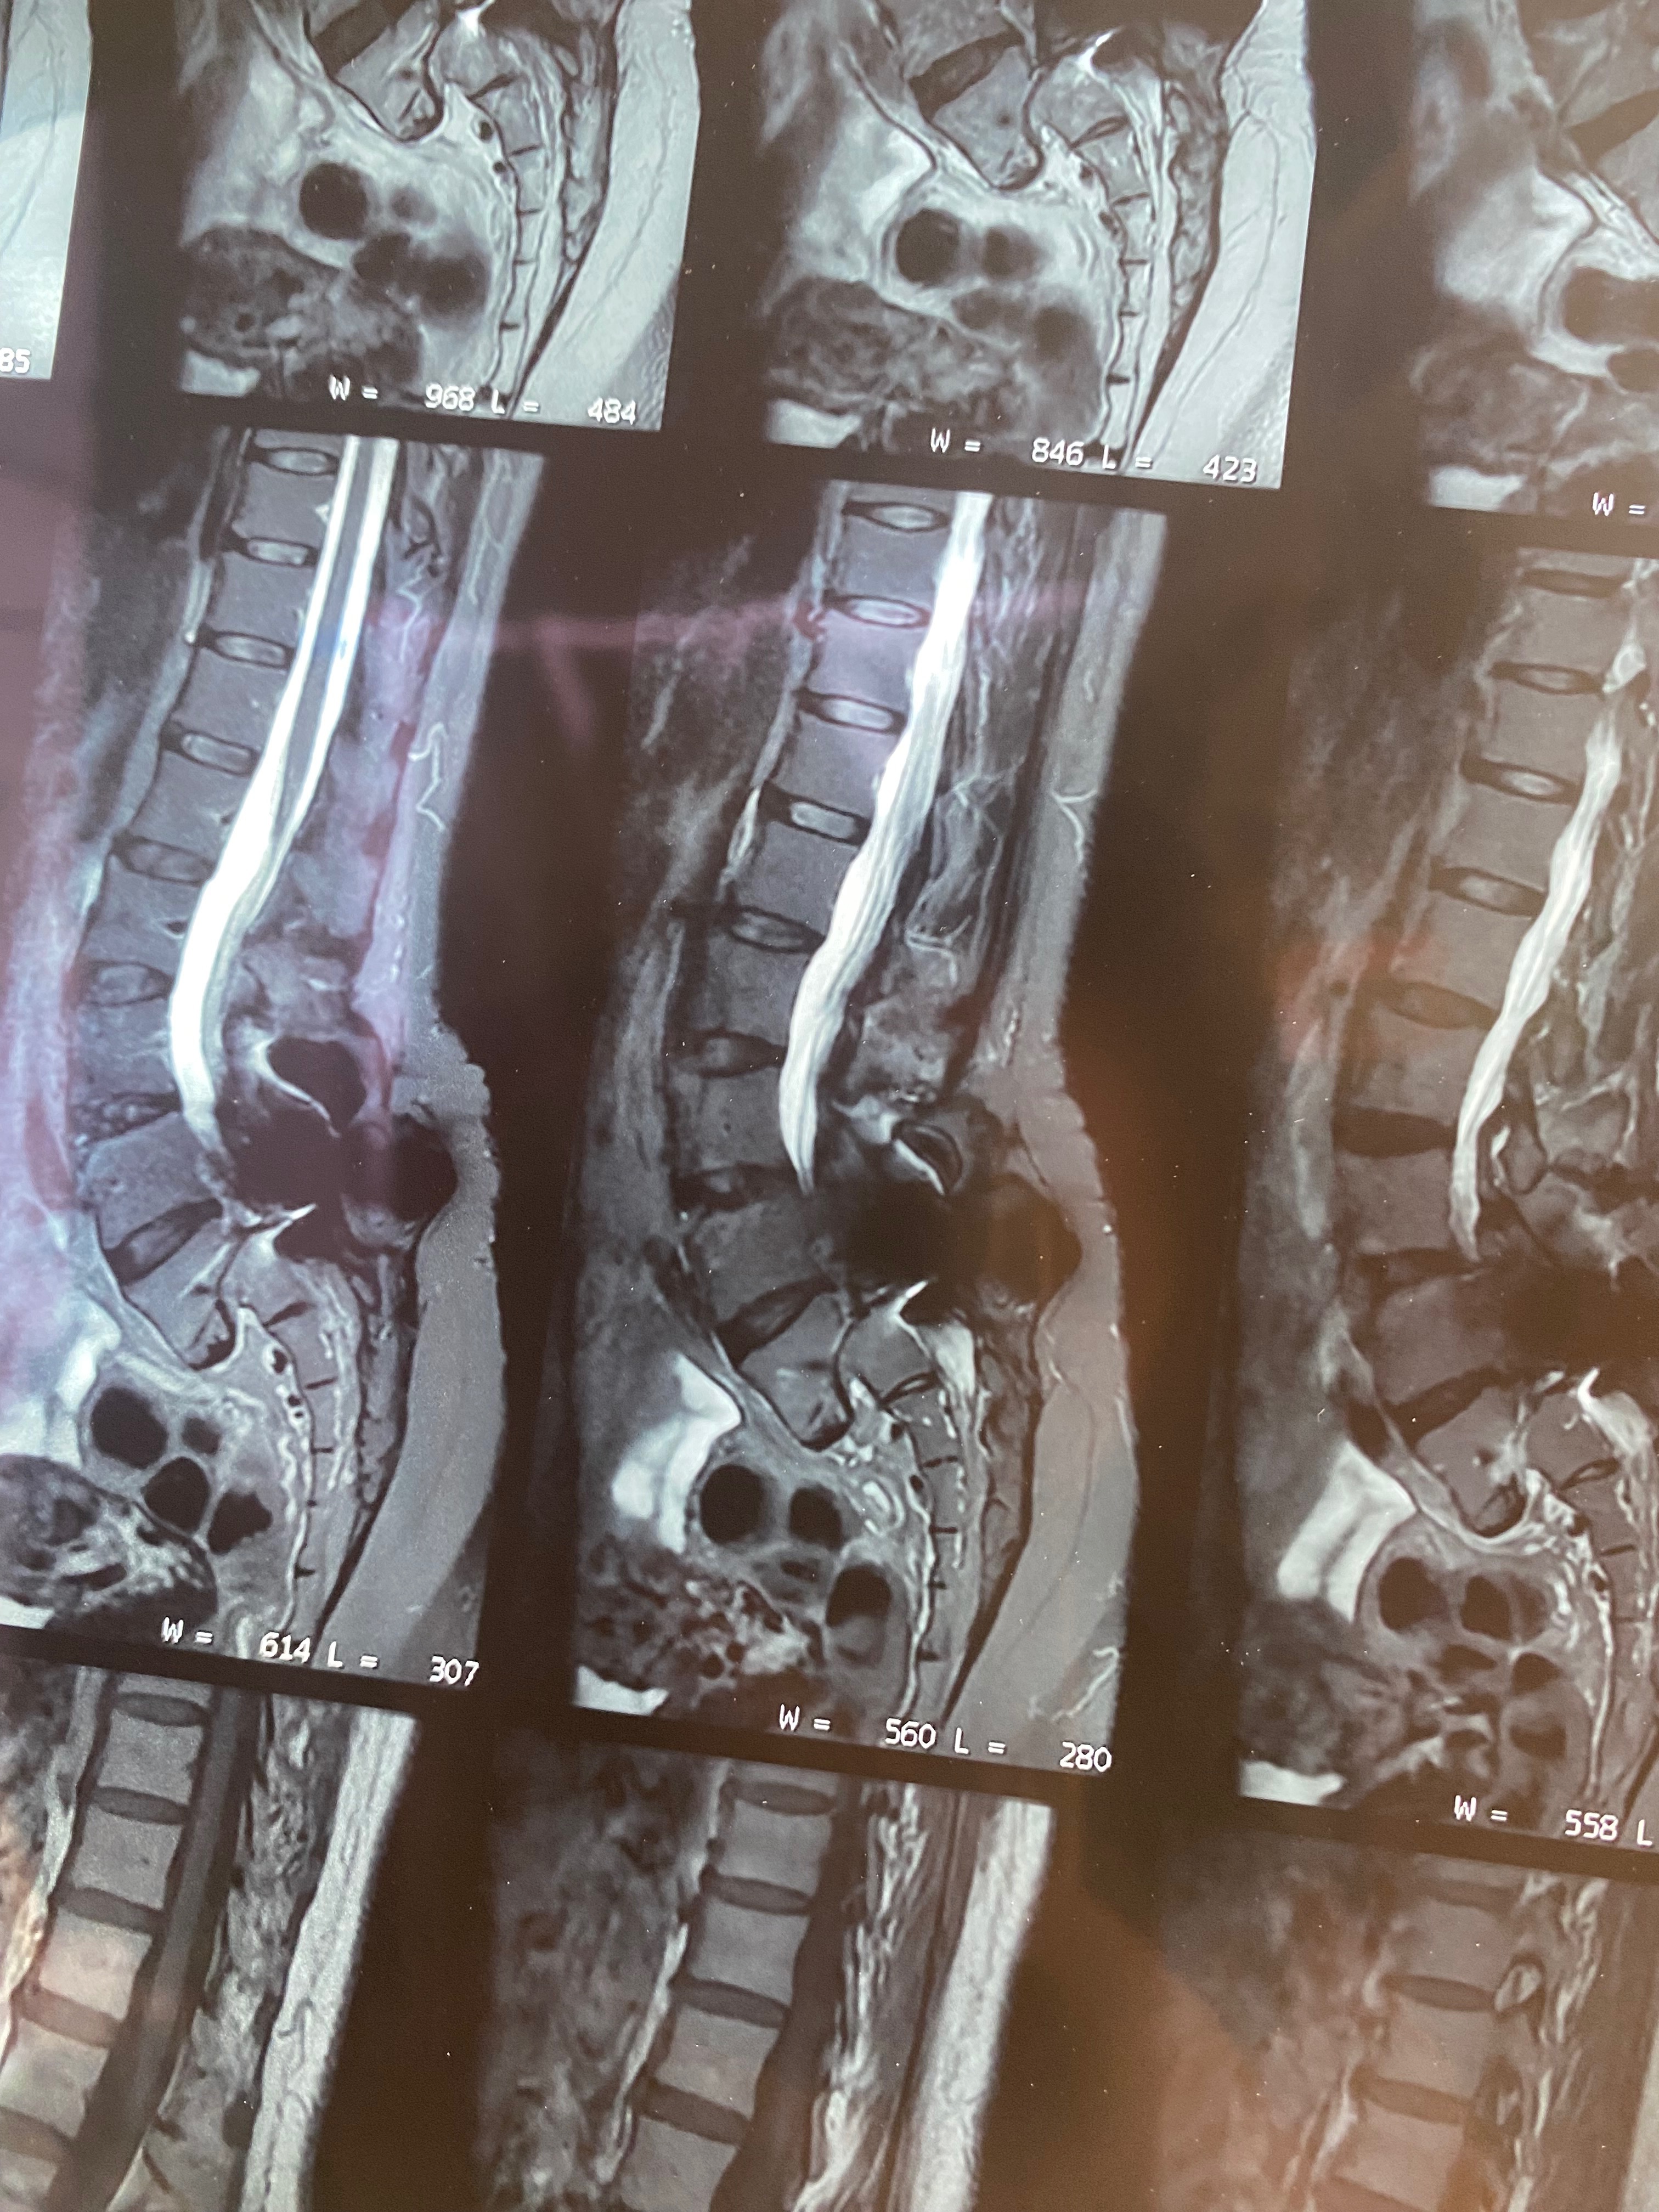

Hace 28 años, mi mamá fue operada de la columna y le colocaron prótesis de metal que, con el paso del tiempo, dejaron de ser funcionales. En los últimos meses, su condición ha empeorado: presenta dolor constante, adormecimiento en las piernas, mareos y una dificultad cada vez mayor para caminar, sentarse y descansar.

Buscamos atención en el sistema de salud público, pero nos informaron que no cuentan con el material necesario ni realizan este tipo de cirugía. Los médicos fueron claros: la intervención no es opcional. Si no se realiza a tiempo, mi mamá corre el riesgo de perder la capacidad de caminar.